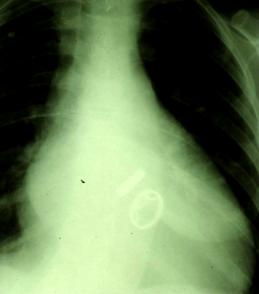

SOSTITUZIONE VALVOLARE MITRO-AORTICA RX TORACE IN PAZ. CON DOPPIA PROTESI

La durata di una protesi meccanica e' praticamente illimitata, ma il principale svantaggio di queste valvole e' dato dalla loro trombogenicità e quindi dalla necessità di seguire una terapia anticoagulante per tutta la vita. Infatti il sangue, a contatto con il carbonio ( come con qualunque materiale artificiale ) e soprattutto nelle zone della valvola a flussi più bassi, tende a formare dei coaguli che potrebbero bloccare il funzionamento della protesi o andare in circolo determinando pericolose tromboembolie. Il paziente dovrà quindi assumere ogni giorno una certa dose di farmaco anticoagulante ( warfarin o dicumarolici ) e dovrà sottoporsi periodicamente ad un prelievo di sangue per il controllo del livello di anticoagulazione ( se troppo basso, il sangue tenderà a coagulare ugualmente, se troppo alto il paziente corre il rischio di emorragie ).